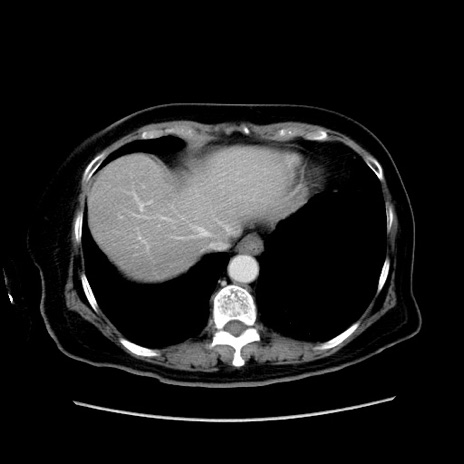

症例19(横断像)

【症例】80歳代女性

【主訴】下腹部痛

【現病歴】約8時間前より下腹部痛の出現あり、救急外来受診。

【既往歴】両側付属器切除

【身体所見】意識清明、下腹部正中に手術痕あり、その部位に一致して圧痛と反跳痛あり。腸蠕動音は亢進。

【データ】WBC 9300、CRP 0.15